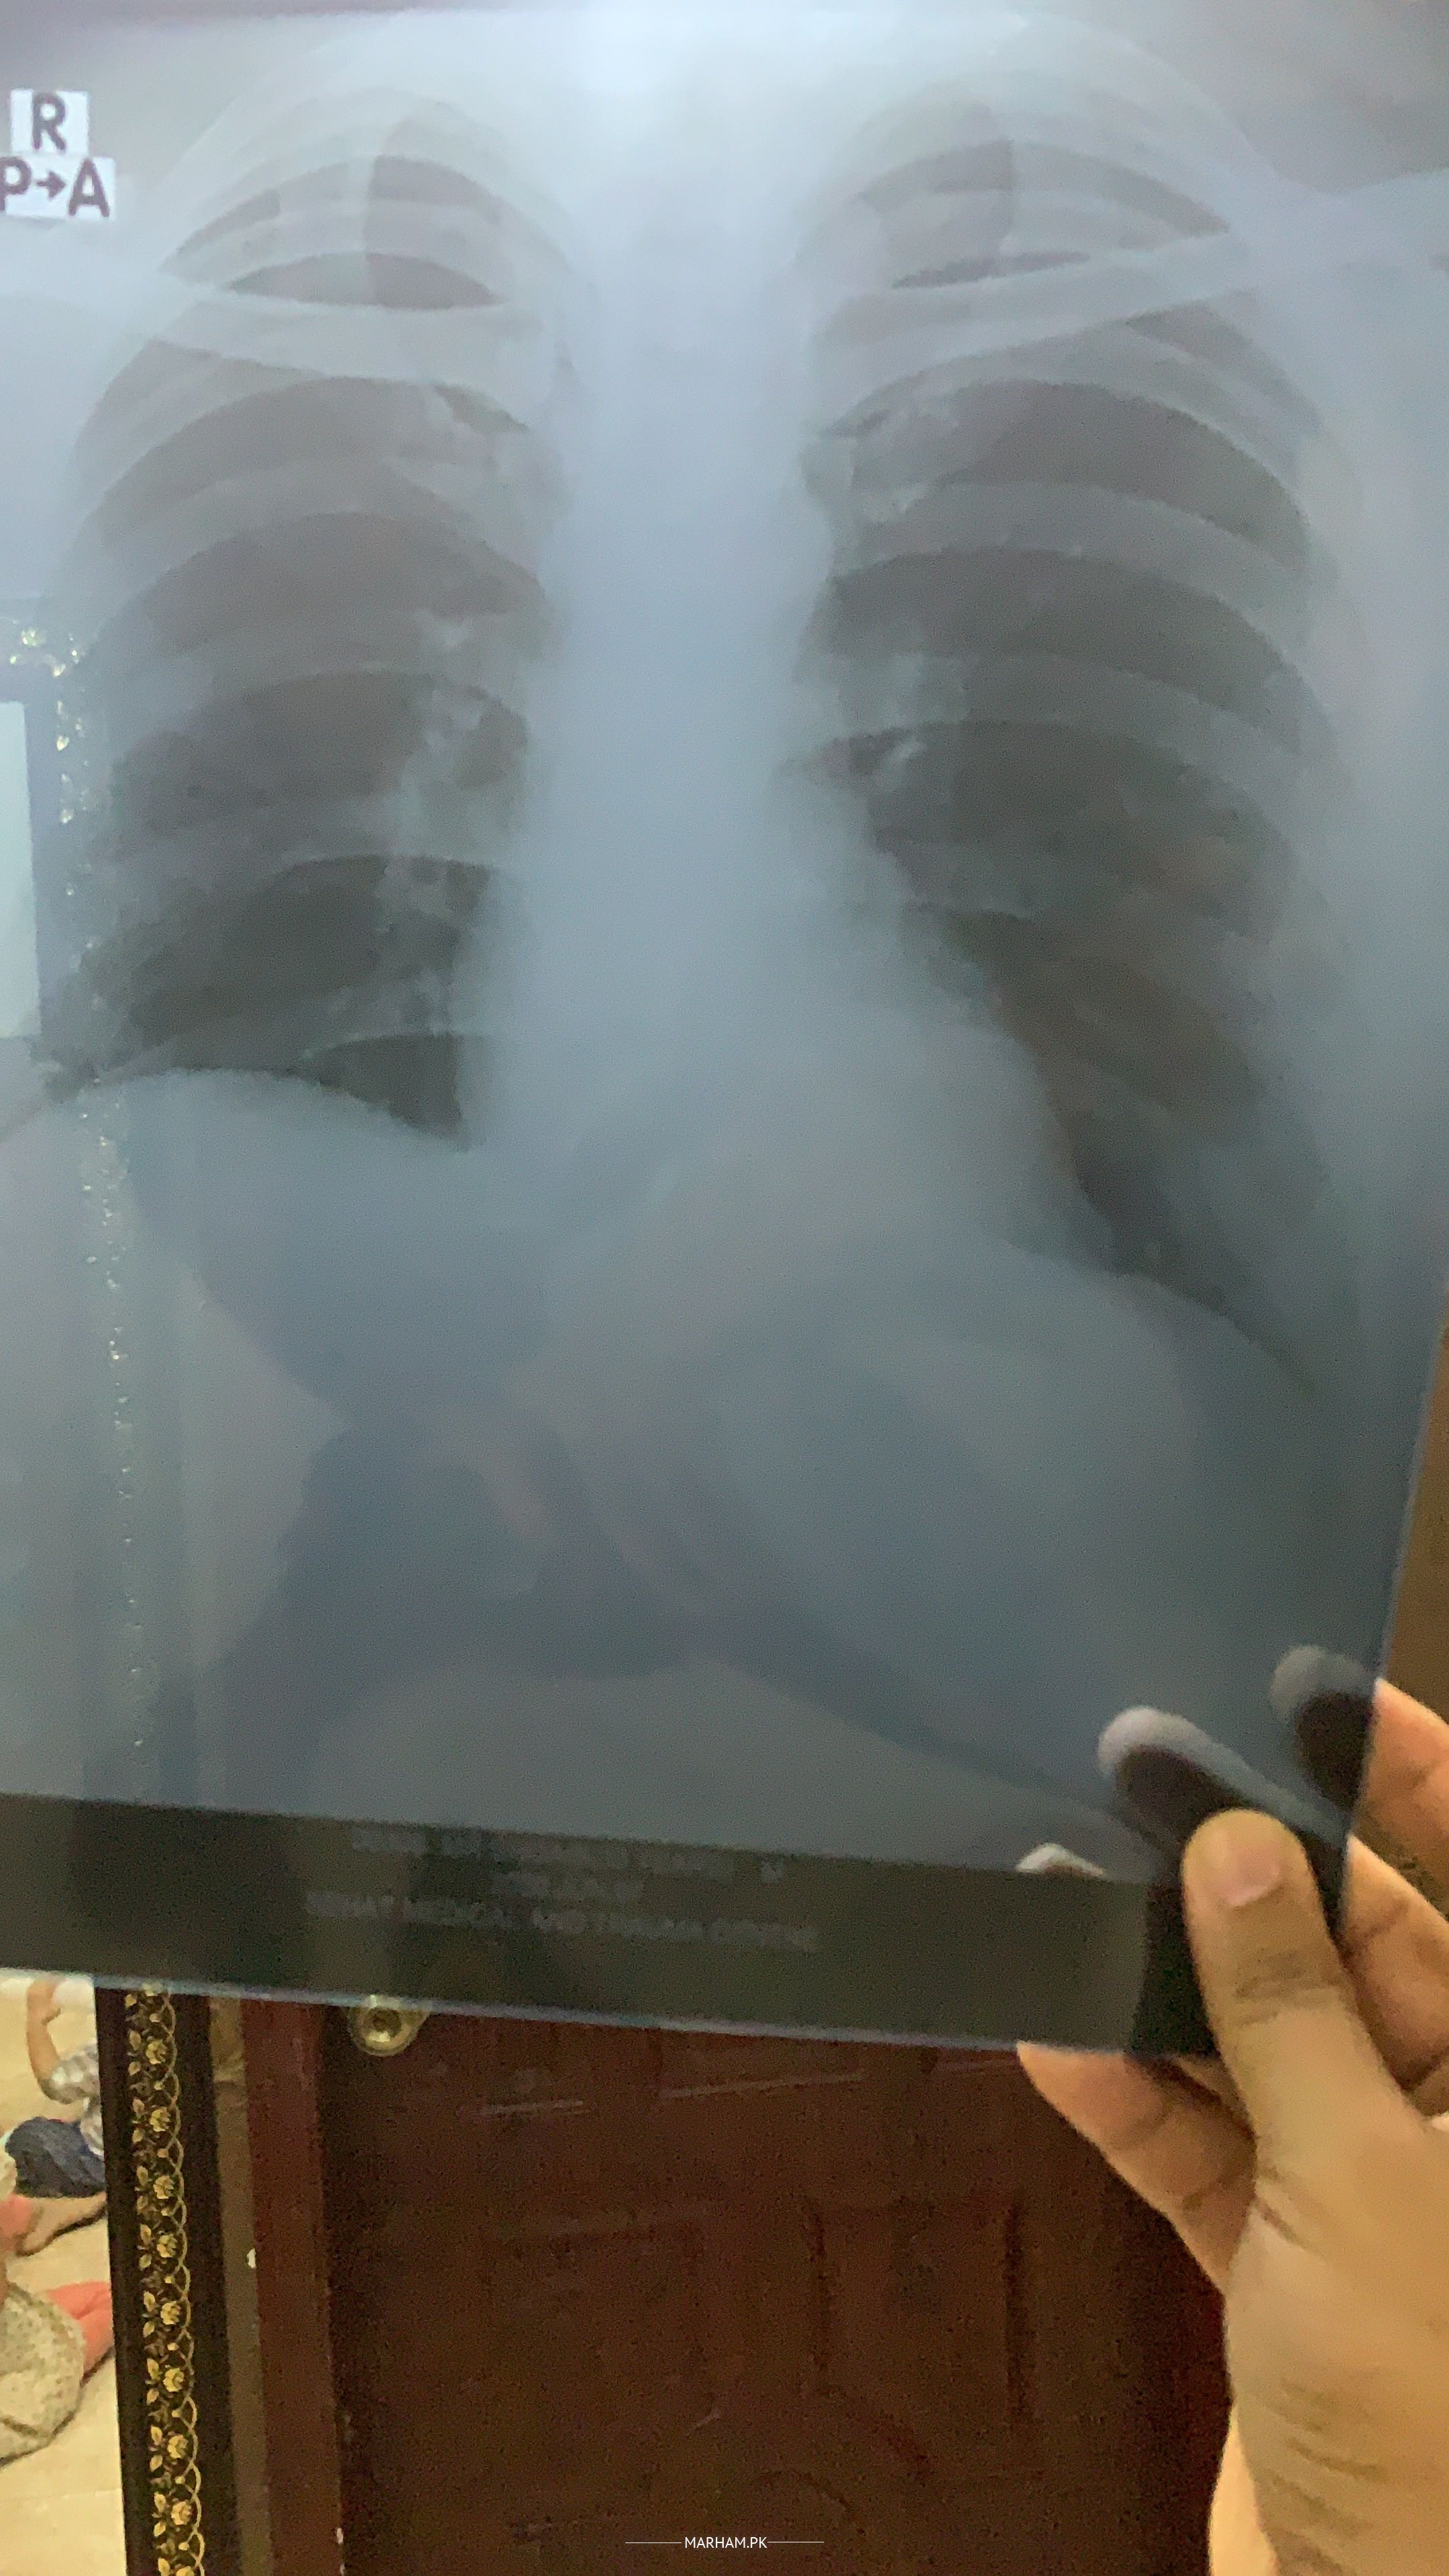

From last 8 days I had little cough with phelgm. In start only for 2 days I had fever 99 and 100. Now no fever no other symptoms. Just want to know is this coronavirus symptoms. Posting my today cbc and chest X-ray thanks.

Normal xray shows cbc is also normal thanks